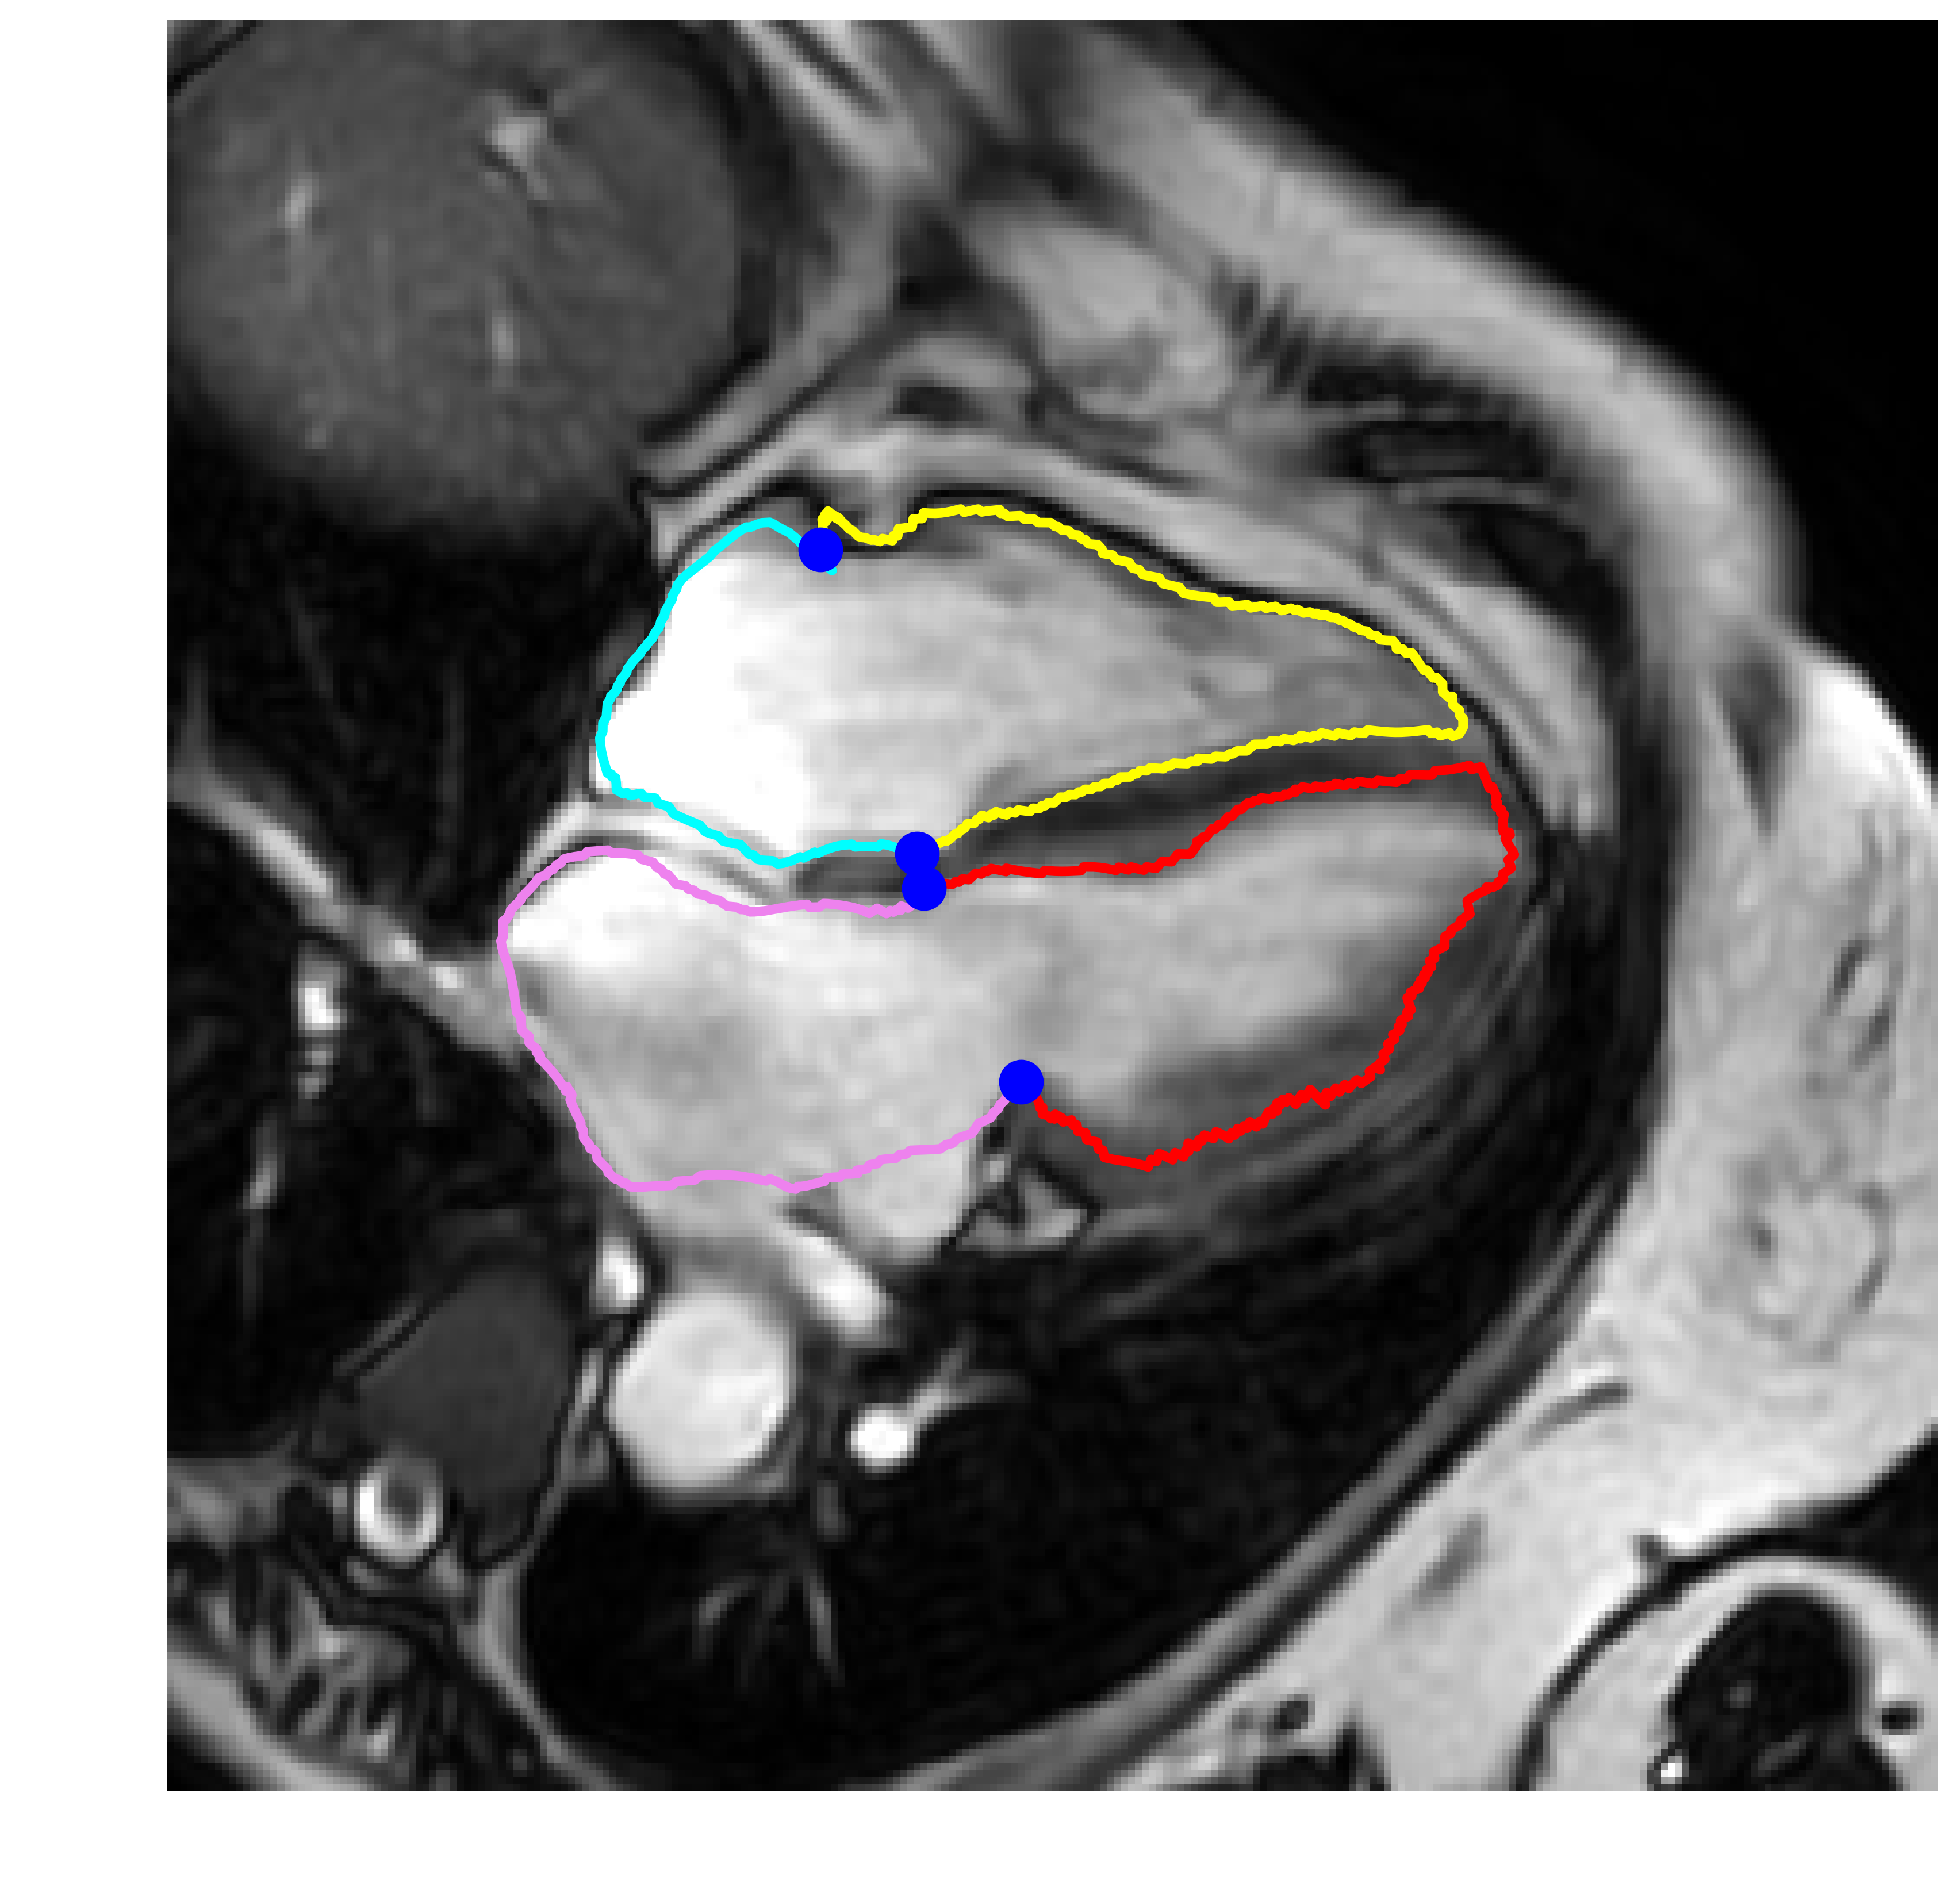

This study utilized a cohort of 374 subjects with 2D+t cine-MRI scans, with each subject having a 4-chamber long-axis (LAX) view. The scans were randomly selected from the ASPIRE registry [Hurdman et al., 2012], and were acquired using a balanced steady state free precession (bSSFP) sequence. The ASPIRE registry included patients with a wide range of pathologies including left heart disease (15%), lung disease (12%), chronic thromboembolic pulmonary arterial hypertension (PAH) (21%), PAH (29%), other PAH (2%) and non-PAH (21%). The scans were acquired using Siemens (n=41) and GE scanners (n=333). The dataset was split into 80% for training (n=300) and 20% for validation (n=74) scans. The training/validation split was stratified based on the scanner. Specifically, out of the 300 scans used for training, 33 scans were from Siemens, and 267 scans were from GE. For the validation set, consisting of 74 scans, 8 scans were from Siemens, and 66 scans were from GE. Expert manual contours for the left ventricle (LV), right ventricle (RV), LV myocardium (LVM), left atrium (LA) and right atrium (RA) were defined in all temporal frames by four observers with 2, 3, 11, and 13 years of CMR experience [Alandejani et al., 2022]. The number of frames per scan ranged from 20 to 30. Each scan corresponds to a complete cardiac cycle. The image series and corresponding contours were center-cropped and resampled into image stacks of size . These images maintain an in-plane resolution of mm, with a total of 25 time frames. The image stacks were normalized to have intensity values between [0, 1]. A total of four landmark points were defined based on the manual contours, these points represented the hinge points of the mitral and tricuspid valves as shown in Fig. 3. These anatomical locations represent the regions with the largest cardiac motion amplitude and are used for the evaluation of the GW registration. Figure 2 illustrates the diversity and variation present in the dataset, as seen through samples depicting a range of field of views, noise levels, contrasts, heart sizes, and orientations.

Figure 4 shows visual examples for the contours, DVF, and determinant of the Jacobian estimated from the proposed method. Figure 5 shows a visual comparison between elastix, Group-RegNet and proposed network against the manually defined contours. It shows that the proposed method achieves better results compared to the other methods especially at the landmark points.